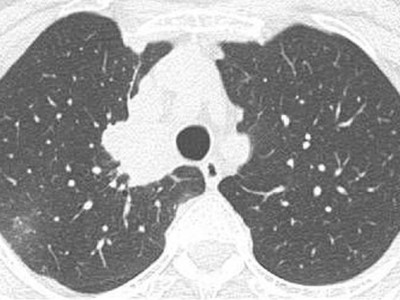

Der besondere Fall: Hyponatriämie bei einer 58-Jährigen mit Lungenkarzinom

Manche Patienten mit nichtkleinzelligem Lungenkarzinom erfahren bei Progress unter zielgerichteter Therapie eine Tumortransformation. Dann ist es nötig, erneut zu biopsieren – so wie im folgenden Fall.

Hyponatriämie bei einem EGFR-positiven pulmonalen Adenokarzinom

Die Patientin entwickelte unter einer Tyrosinkinaseinhibitor-Therapie eine schwere Hyponatriämie – u.a. mit begleitenden Konzentrationsstörungen. Handelt es sich um ein Fortschreiten des Tumors, eine Nebenwirkung der Therapie oder um etwas Anderes?

Kind erhält Leukämie Therapie/© FatCamera / Getty Images / iStock (Symbolbild mit Fotomodell), Immuncheckpointinhibitoren binden an Krebszelloberflächenproteine /© Juan Gärtner / stock.adobe.com, Arzt misst Blutzucker per Glucometer/© geargodz / Stock.adobe.com (Symbolbild mit Fotomodell), CT der Lunge mit Konsolidierungen (Pfeile) und Milchglastrübungen bei einer immunvermittelten Pneumonitis/© Minuth-Fuchs, K.L., Schulz, C. / all rights reserved Springer Medizin Verlag GmbH, Hepatozelluläres Karzinom im Lebersegment VIII/© Wengert, G. et al. / all rights reserved Springer Medizin Verlag GmbH, Blutabstrich der chonisch lymphatischen Leukämie/© jarun011 / Getty Images / iStock, Endobronchialer Befund mit exophytischem Tumor im Bereich des rechten Oberlappens/© Möller, M., Schütte, W. / all rights reserved Springer Medizin Verlag GmbH, Mann nimmt eine Tablette ein/© Jelena Stanojkovic / stock.adobe.com (Symbolbild mit Fotomodell), Thymom mit pleuraler Aussaat rechts im Masaoka-Koga-Stadium IVa./© Ried, M. et al. / all rights reserved Springer Medizin Verlag GmbH, Patientin schaut besorgt auf Infusionsbeutel/© KatarzynaBialasiewicz / Getty Images / iStock (Symbolbild mit Fotomodellen), Ältere Frau nimmt Tablette ein/© amenic181 / stock.adobe.com (Symbolbild mit Fotomodell), Generalisierte, konfluierende, kokardenartige Erytheme mit zentraler Blase/© Springer Medizin Verlag GmbH, Bronchialkarzinom/© Dr. Myriam Koch , Pulmonales Adenokarzinom bei Diagnosestellung/© Springer Medizin, Bestrahlung eines Lungenkarzinoms/© Springer Medizin Verlag GmbH, Search Icon, Ältere Frau fasst sich an die Brust/© Jelena Stanojkovic / Stock.adobe.com (Symbolbild mit Fotomodell), Person setzt DNS-Probe in Maschine ein/© Vit Kovalcik / stock.adobe.com, Mann raucht Joint/© Daniel Sierralta / Westend61 / stock.adobe.com (Symbolbild mit Fotomodell), Blut in Toilette/© stylefoto24 / stock.adobe.com